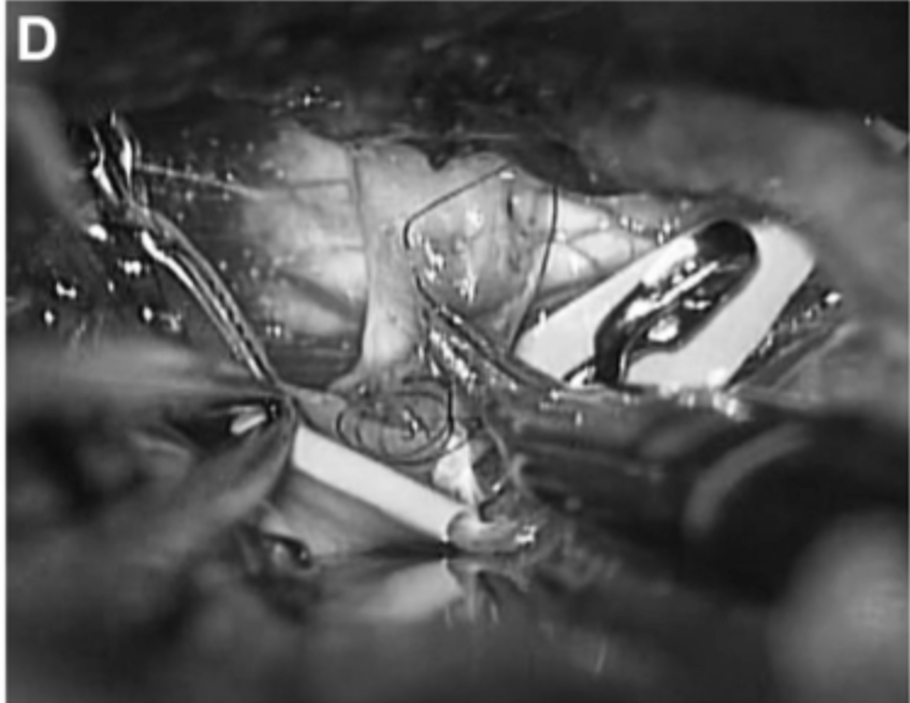

▼20天,经左颞下入路进行动脉瘤鼓励术和STA-PCA搭桥重建手术。初期夹闭动脉瘤的近端部分,同时保留丘脑穿支动脉。动脉瘤的解剖区域延伸到P2段后部,就在PTA分支点之前。在本例中,选择PTA作为受体动脉,因为其口径和角度优于P3段进行吻合(图3C和3D)。

C、D,受体动脉的PTA(箭头)。通过左颞下入路缝合STA和PTA之间的吻合。